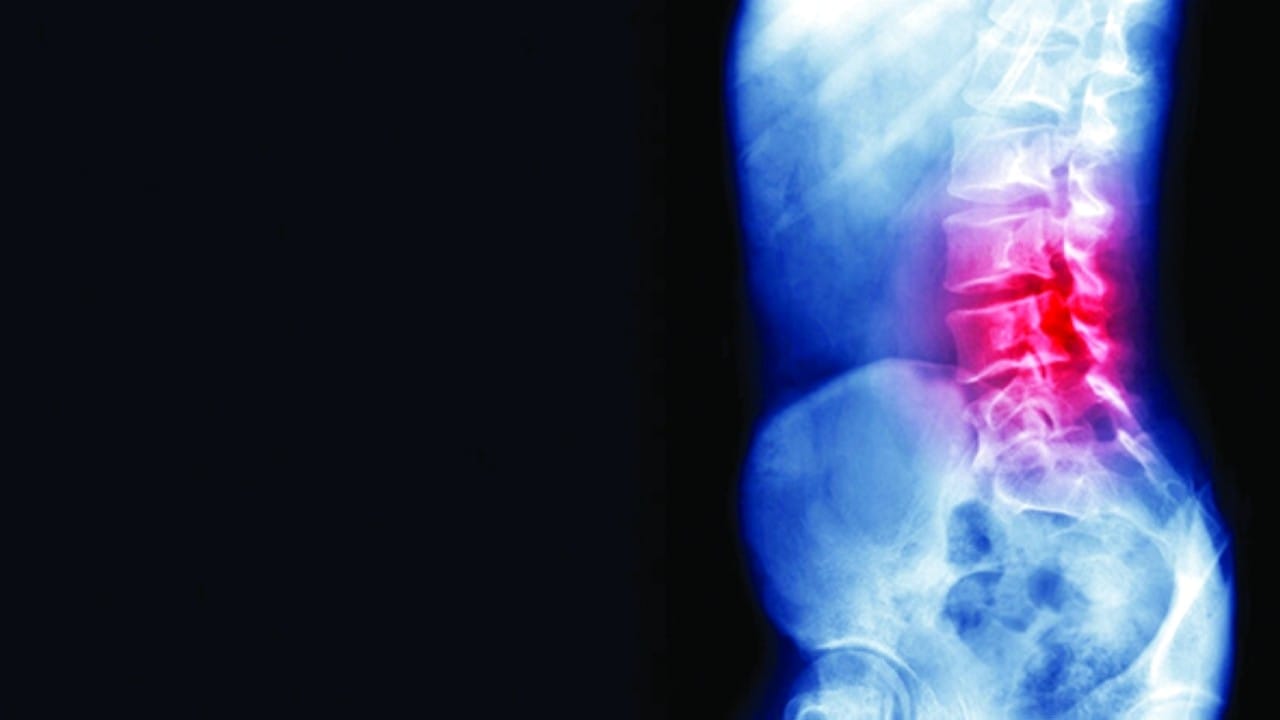

الأشعة السينية

غاز الضحك يدمر العمود الشوكي لرجل